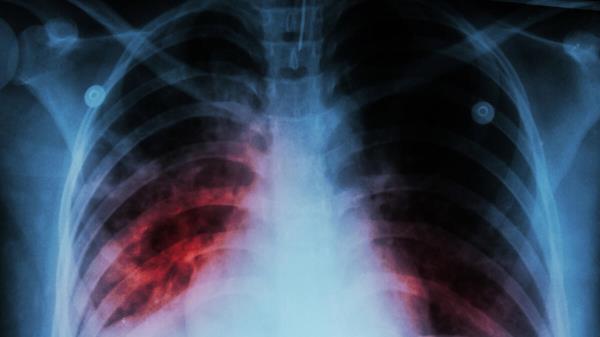

“当鼻喷DNA融合疫苗与一线结核药物联合使用时,受感染小鼠的病原菌清除速度显著加快,肺部炎症减轻,治疗结束后更有效防止了病情复发。”研究负责人斯泰利亚尼·卡拉尼卡强调。她身兼约翰斯·霍普金斯大学结核病研究中心核心成员与医学院助理教授双职,该结论已通过校方官网发布。

据世界卫生组织界定,结核病是由细菌引发的传染性疾病,通常通过咳嗽传播并侵袭肺部。2024年全球新增感染超1000万例中,约120万人因此丧生;全球约四分之一人口携带结核杆菌而无症状,其中5%至10%会发展为活动性结核病。婴幼儿一旦感染,患病风险尤为突出。

典型症状包括持续咳嗽(有时带血)、胸痛、虚弱乏力、体重下降、发热及夜间盗汗。该病通常需抗生素治疗,若放任不管可能致命。